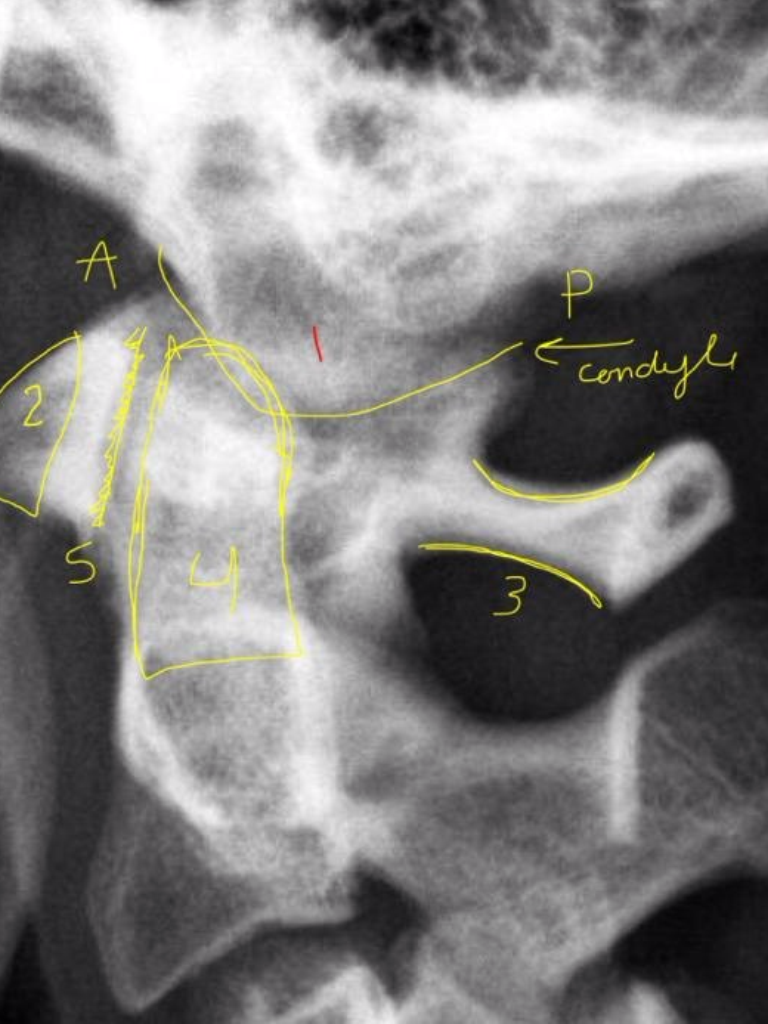

14

1

A

Occipital Condyle

(anterior/posterior)

15

2

Anterior Tubercle C1

16

3

Posterior Arch C1

17

4

Odontoid Process C2

18

5

Atlanto-Dental Interspace